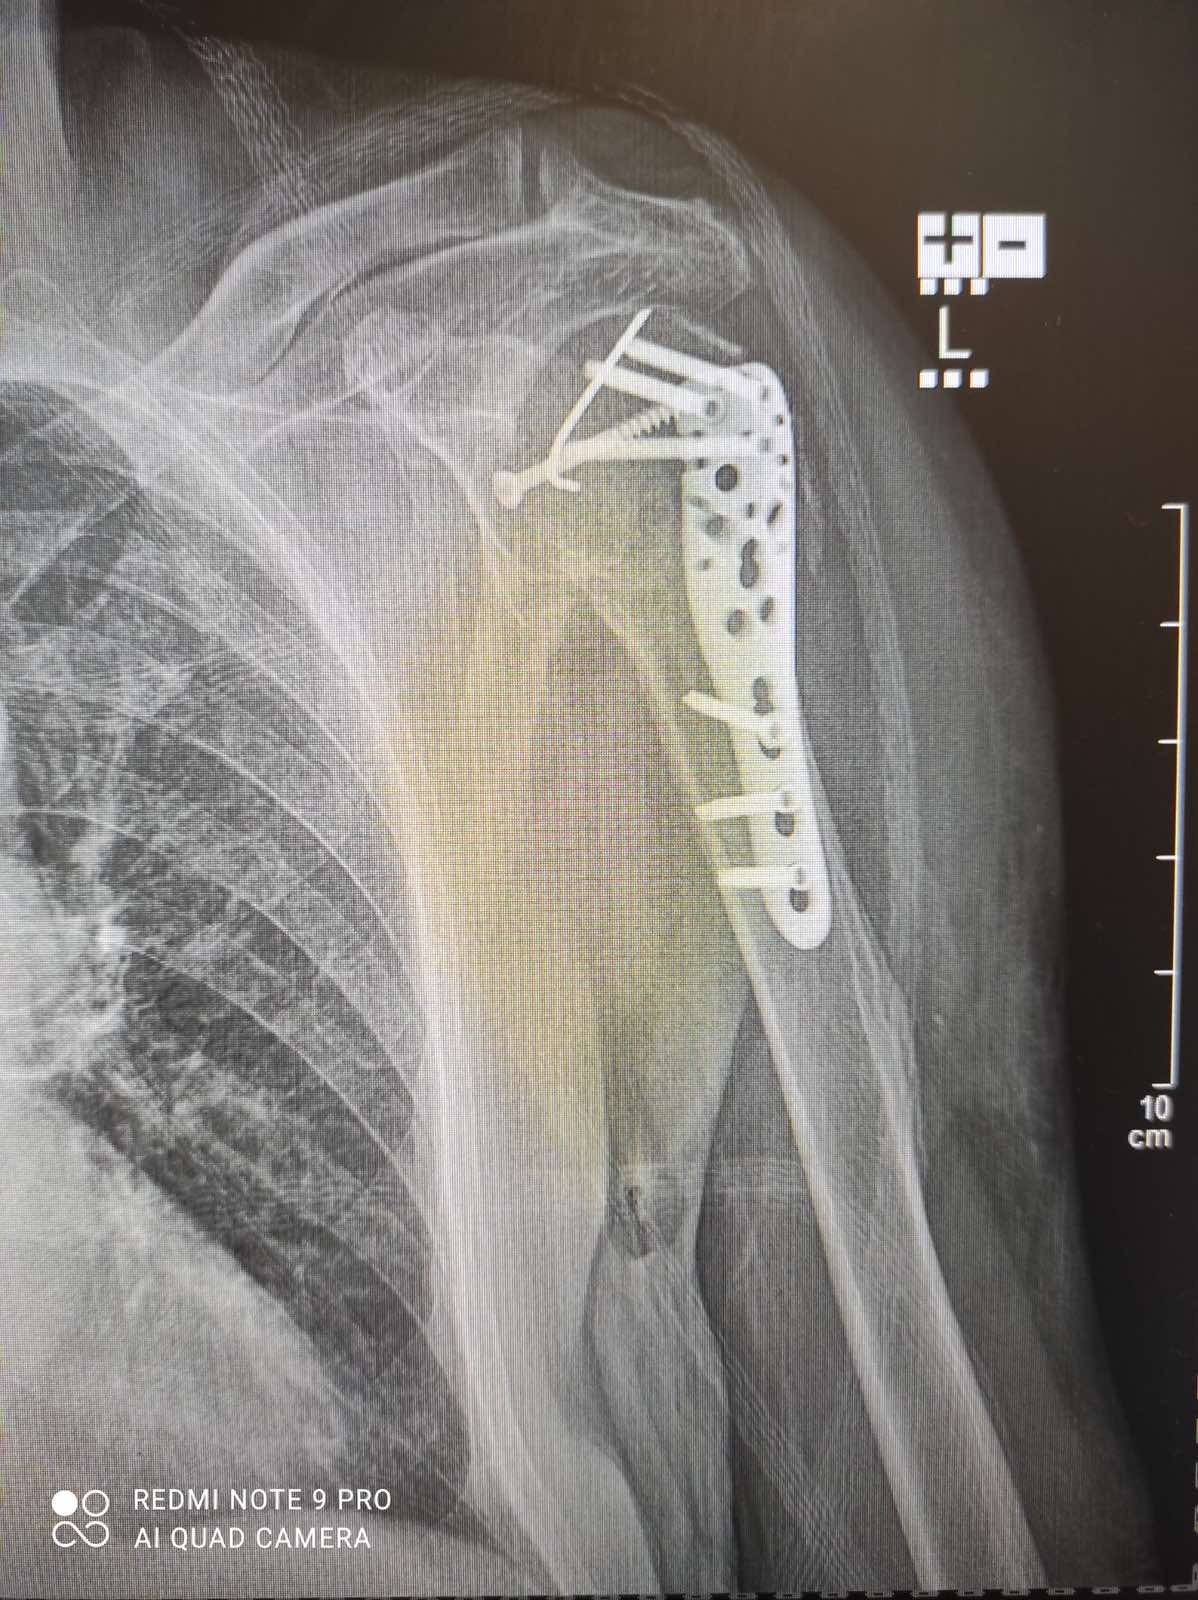

Моя мама потрапила до нього зі складним випадком — перелом в області плеча. Ситуація вимагала високої точності, досвіду та швидких рішень. Операція пройшла швидко та успішно.

Особливо цінною стала його людяність. Мирослав Ігорович уважно ставився до мами, детально пояснював кожен крок, створював відчуття спокою та впевненості. Для мене, як для доньки, це мало величезне значення — я відчувала підтримку та залученість лікаря на кожному етапі.

Окремо хочу відзначити його лідерські якості. Він згуртував медичну команду, вибудував чітку роботу всього процесу та забезпечив високий рівень супроводу в лікарні. Навіть у державному закладі вдалося створити комфортні умови для пацієнтки.